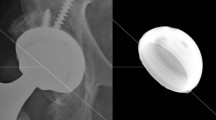

Test coupons were created for this study to be representative of an investigational mobile-bearing design (Simplify Medical, Sunnyvale, CA, USA). The geometry of this design is based on the KineFlex®|C Cervical TDR (SpinalMotion, Mountain View, CA, USA). The test coupons in the present study were comprised of two PEEK endplates (PEEK® Optima Natural; Invibio, West Conshohocken, PA, USA) separated by a mobile zirconia-toughened alumina ceramic core (CeraSurf®-p; CoorsTek® Medical, Grand Junction, CO, USA) (Fig. 1). The titanium plasma spray coating and other surface features that are normally present on the bone-contacting surfaces of the endplates were omitted per ASTM F2423 for ease of fixturing and to preclude third-body wear from compromising the evaluation of the articulating surfaces. The endplate footprints were all 14 × 16 mm with the exception of the impingement wear samples. Two sizes, small (12 × 15 mm) and large (16 × 18 mm), were evaluated under impingement conditions. All samples were subjected to 25 kGy terminal sterilization before testing.

(A1–A3) Representative superior endplate, core, and inferior endplate after idealized wear testing are shown. (B1–B3) Representative superior endplate, core, and inferior endplate after impingement wear testing for the small size components. (C1–C3) Representative superior endplate, core, and inferior endplate after impingement wear testing for the large size components. The red arrows in images B1–B3 and C3 indicate the region of impingement. (D1–D3) Representative superior endplate, core, and inferior endplate after abrasive wear testing. The yellow arrow in C2 indicates the titanium transfer applied to the core for abrasive testing.